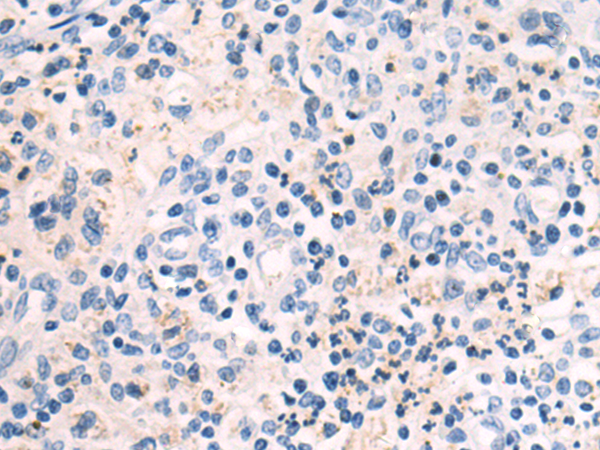

分类: 科研抗体货号: P03994别名: GLUT3应用: WB,IHC反应种属: Human

分类: 科研抗体货号: P03997别名: GLUT10, GLUT11, SLC2A11-a, SLC2A11-c应用: IHC反应种属: Human

分类: 科研抗体货号: P04050别名: MAR, IRF-1应用: WB,IHC反应种属: Human, Mouse, Rat

分类: 科研抗体货号: P03987别名: GDNFR3应用: WB,IHC反应种属: Human, Mouse

分类: 科研抗体货号: P03985别名: GDNFR; RET1L; RETL1; TRNR1; GDNFRA; GFR-ALPHA-1应用: WB,IHC反应种属: Human, Mouse, Rat

分类: 科研抗体货号: P04037别名: HECH; HP1-GAMMA; HP1Hs-gamma应用: WB,IHC反应种属: Human, Mouse

分类: 科研抗体货号: P04072别名: CGB4; HH23; LSH-B; LSH-beta应用: WB,IHC反应种属: Human, Mouse